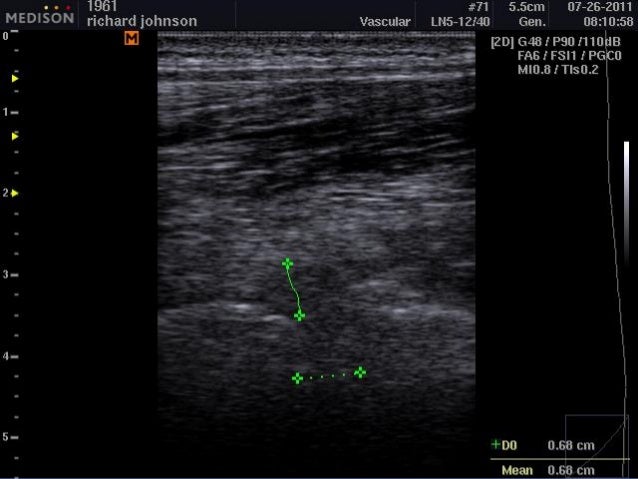

47. US guided injection of an Intervertebral Disc MRI-L4-5 disc herniation US L4-5 disc herniation

48. Case Study-Chris C. (Lumbar Disc Hernation)  PE: VSS; TTP in L side of L4 transverse process; sidebending to the L in lumbar spine exaccerbates condition; tight lumbar paraspinals; laxity at L4-5 interspinous ligament; hypersympathetic state  MRI confirms L sided disc herniation at L4-5  Assessment  Disc herniation with radiculopathy  Sciatic pain  Ligamentous Laxity

49. Case Study-Chris C. (Lumbar Disc Hernation)  Plan:  Injectional treatment using O3 into L4-5 disc  Proliferative injection in L4-5 interspinous ligament  Physcial therapy; traction